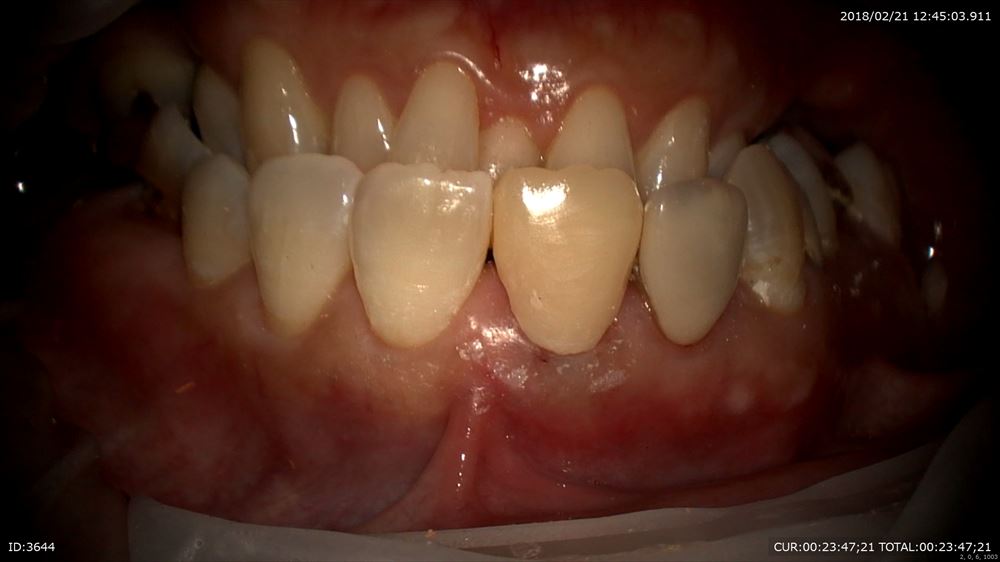

術前と術後

まず前歯から他院で折れているから抜かなければいけないかもとの事。外すと虫歯だらけ。。

確かに亀裂が!!

これを丁寧に除去(マイクロスコープだから安心!)

仮歯を作り

今日は終了

この歯も保存できます。お口全体にトラブルがありますのでカウンセリングでお話しした通り進めていきます。笑顔で帰られて良かった!!